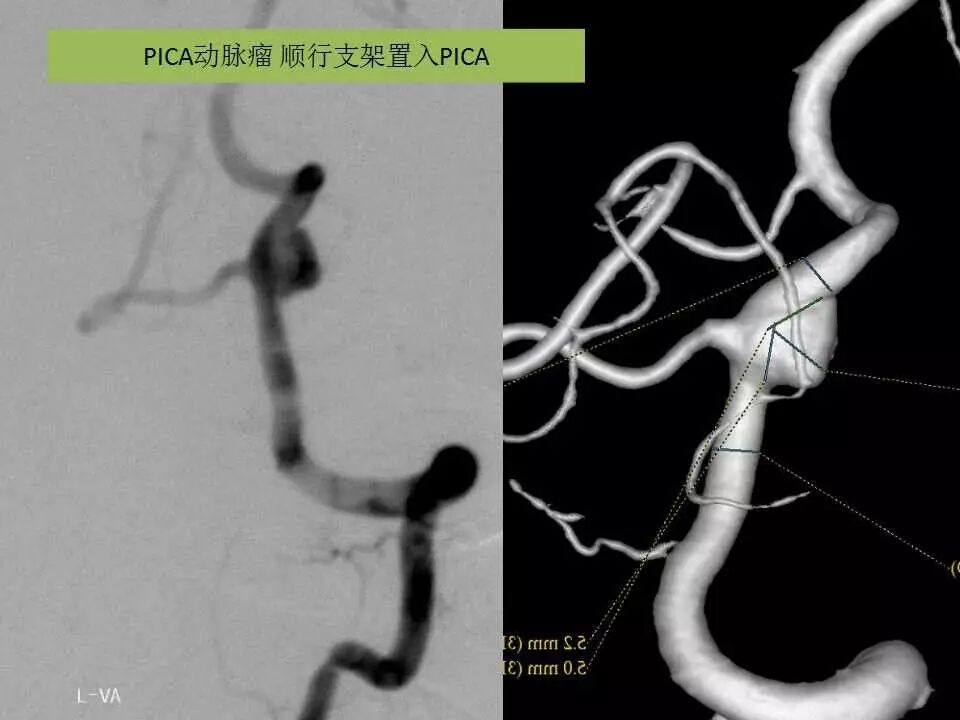

今天为大家分享的是“强生医疗CNV-神经介入专栏”第十五期,由首都医科大学宣武医院何川教授带来的“颅内动脉瘤介入治疗”精彩讲课视频及PPT,欢迎观看、阅读。文章仅代表作者个人观点,如有不同见解,欢迎同道斧正!